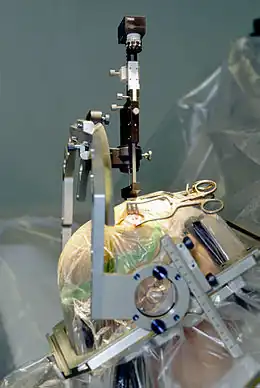

Invasive interventions

Surgery for Parkinson's first appeared in the 19th century and by the 1960s had evolved into ablative brain surgery that lesioned the basal ganglia, thalamus or globus pallidus (a pallidotomy).[189] The discovery of L-DOPA for PD treatment caused ablative therapies to largely disappear.[190][191] Ablative surgeries experienced a resurgence in the 1990s but were quickly superseded by newly-developed deep brain stimulation (DBS).[191] Although gamma knife and high-intensity focused ultrasound surgeries have been developed for pallidotomies and thalamotomies, their use remains rare.[192][193]

DBS involves the implantation of electrodes called neurostimulators, which sends electrical impulses to specific parts of the brain.[163] DBS for the subthalamic nucleus and globus pallidus interna has high efficacy for up to 2 years, but longterm efficacy is unclear and likely decreases with time.[163] A 2024 meta-analysis of DBS treatment in conjunction with antiparkinsonian drugs found improvements primarily in motor function, with serious adverse events largely relating to hardware issues or perioperative events. However, it assessed the evidence relating to both the benefits and harms of DBS as very low quality, owing to high risk of bias and significant methodological issues in trials, possibly leading to overestimation of benefits. Evidence remains insufficient to assess all-cause mortality.[194] DBS typically targets rigidity and tremor,[195] and is recommended for PD patients who are intolerant or do not respond to medication.[164] Cognitive impairment is the most common exclusion criteria.[196]